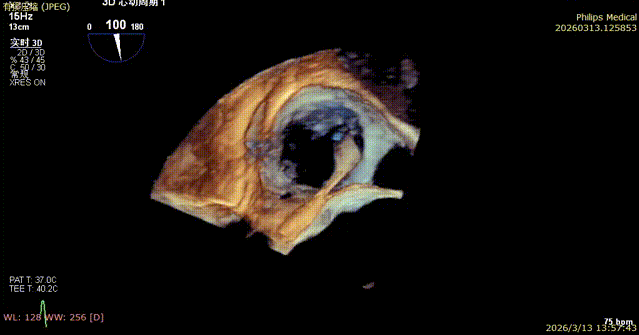

4. After opening the clipping component, the orientation was adjusted under 3D mode.

5. Apposition to the tricuspid annulus under 3D mode.

6. Under the guidance of MultiVue mode and DSA, the anchoring pull rod was retracted and the clipping component was closed to complete the clip application.